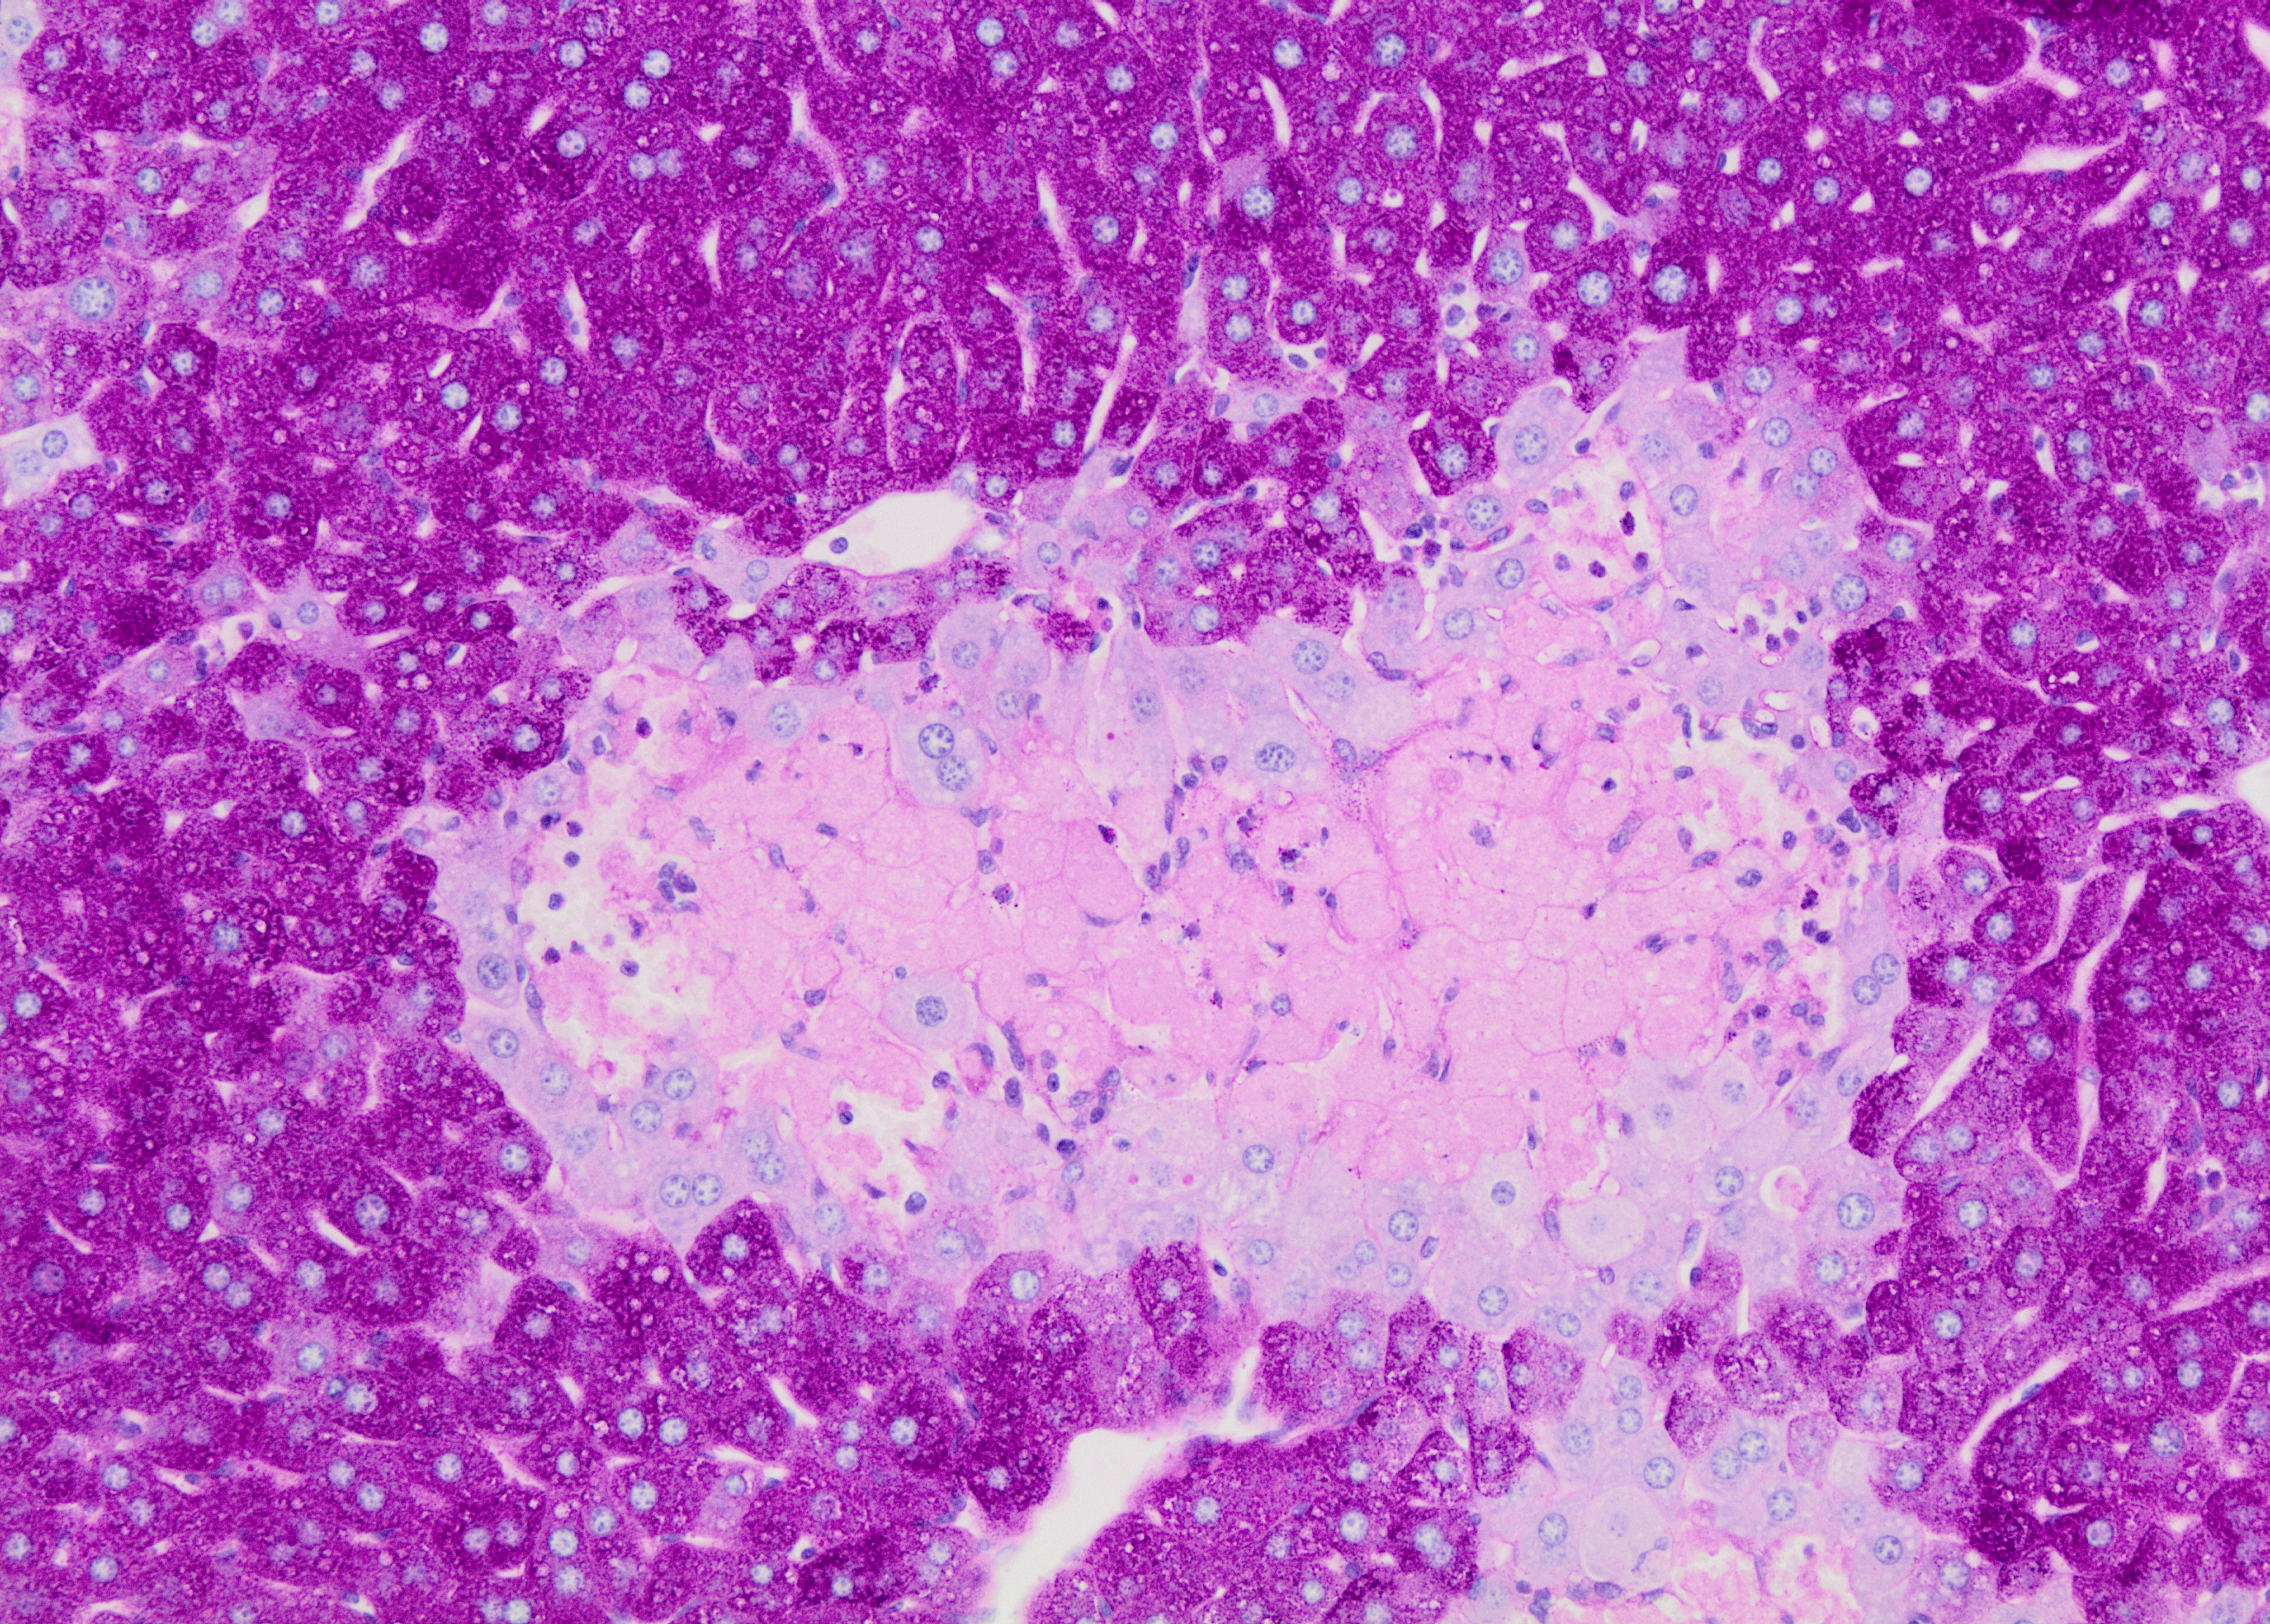

And then here’s some images I’ve taken using a microscope